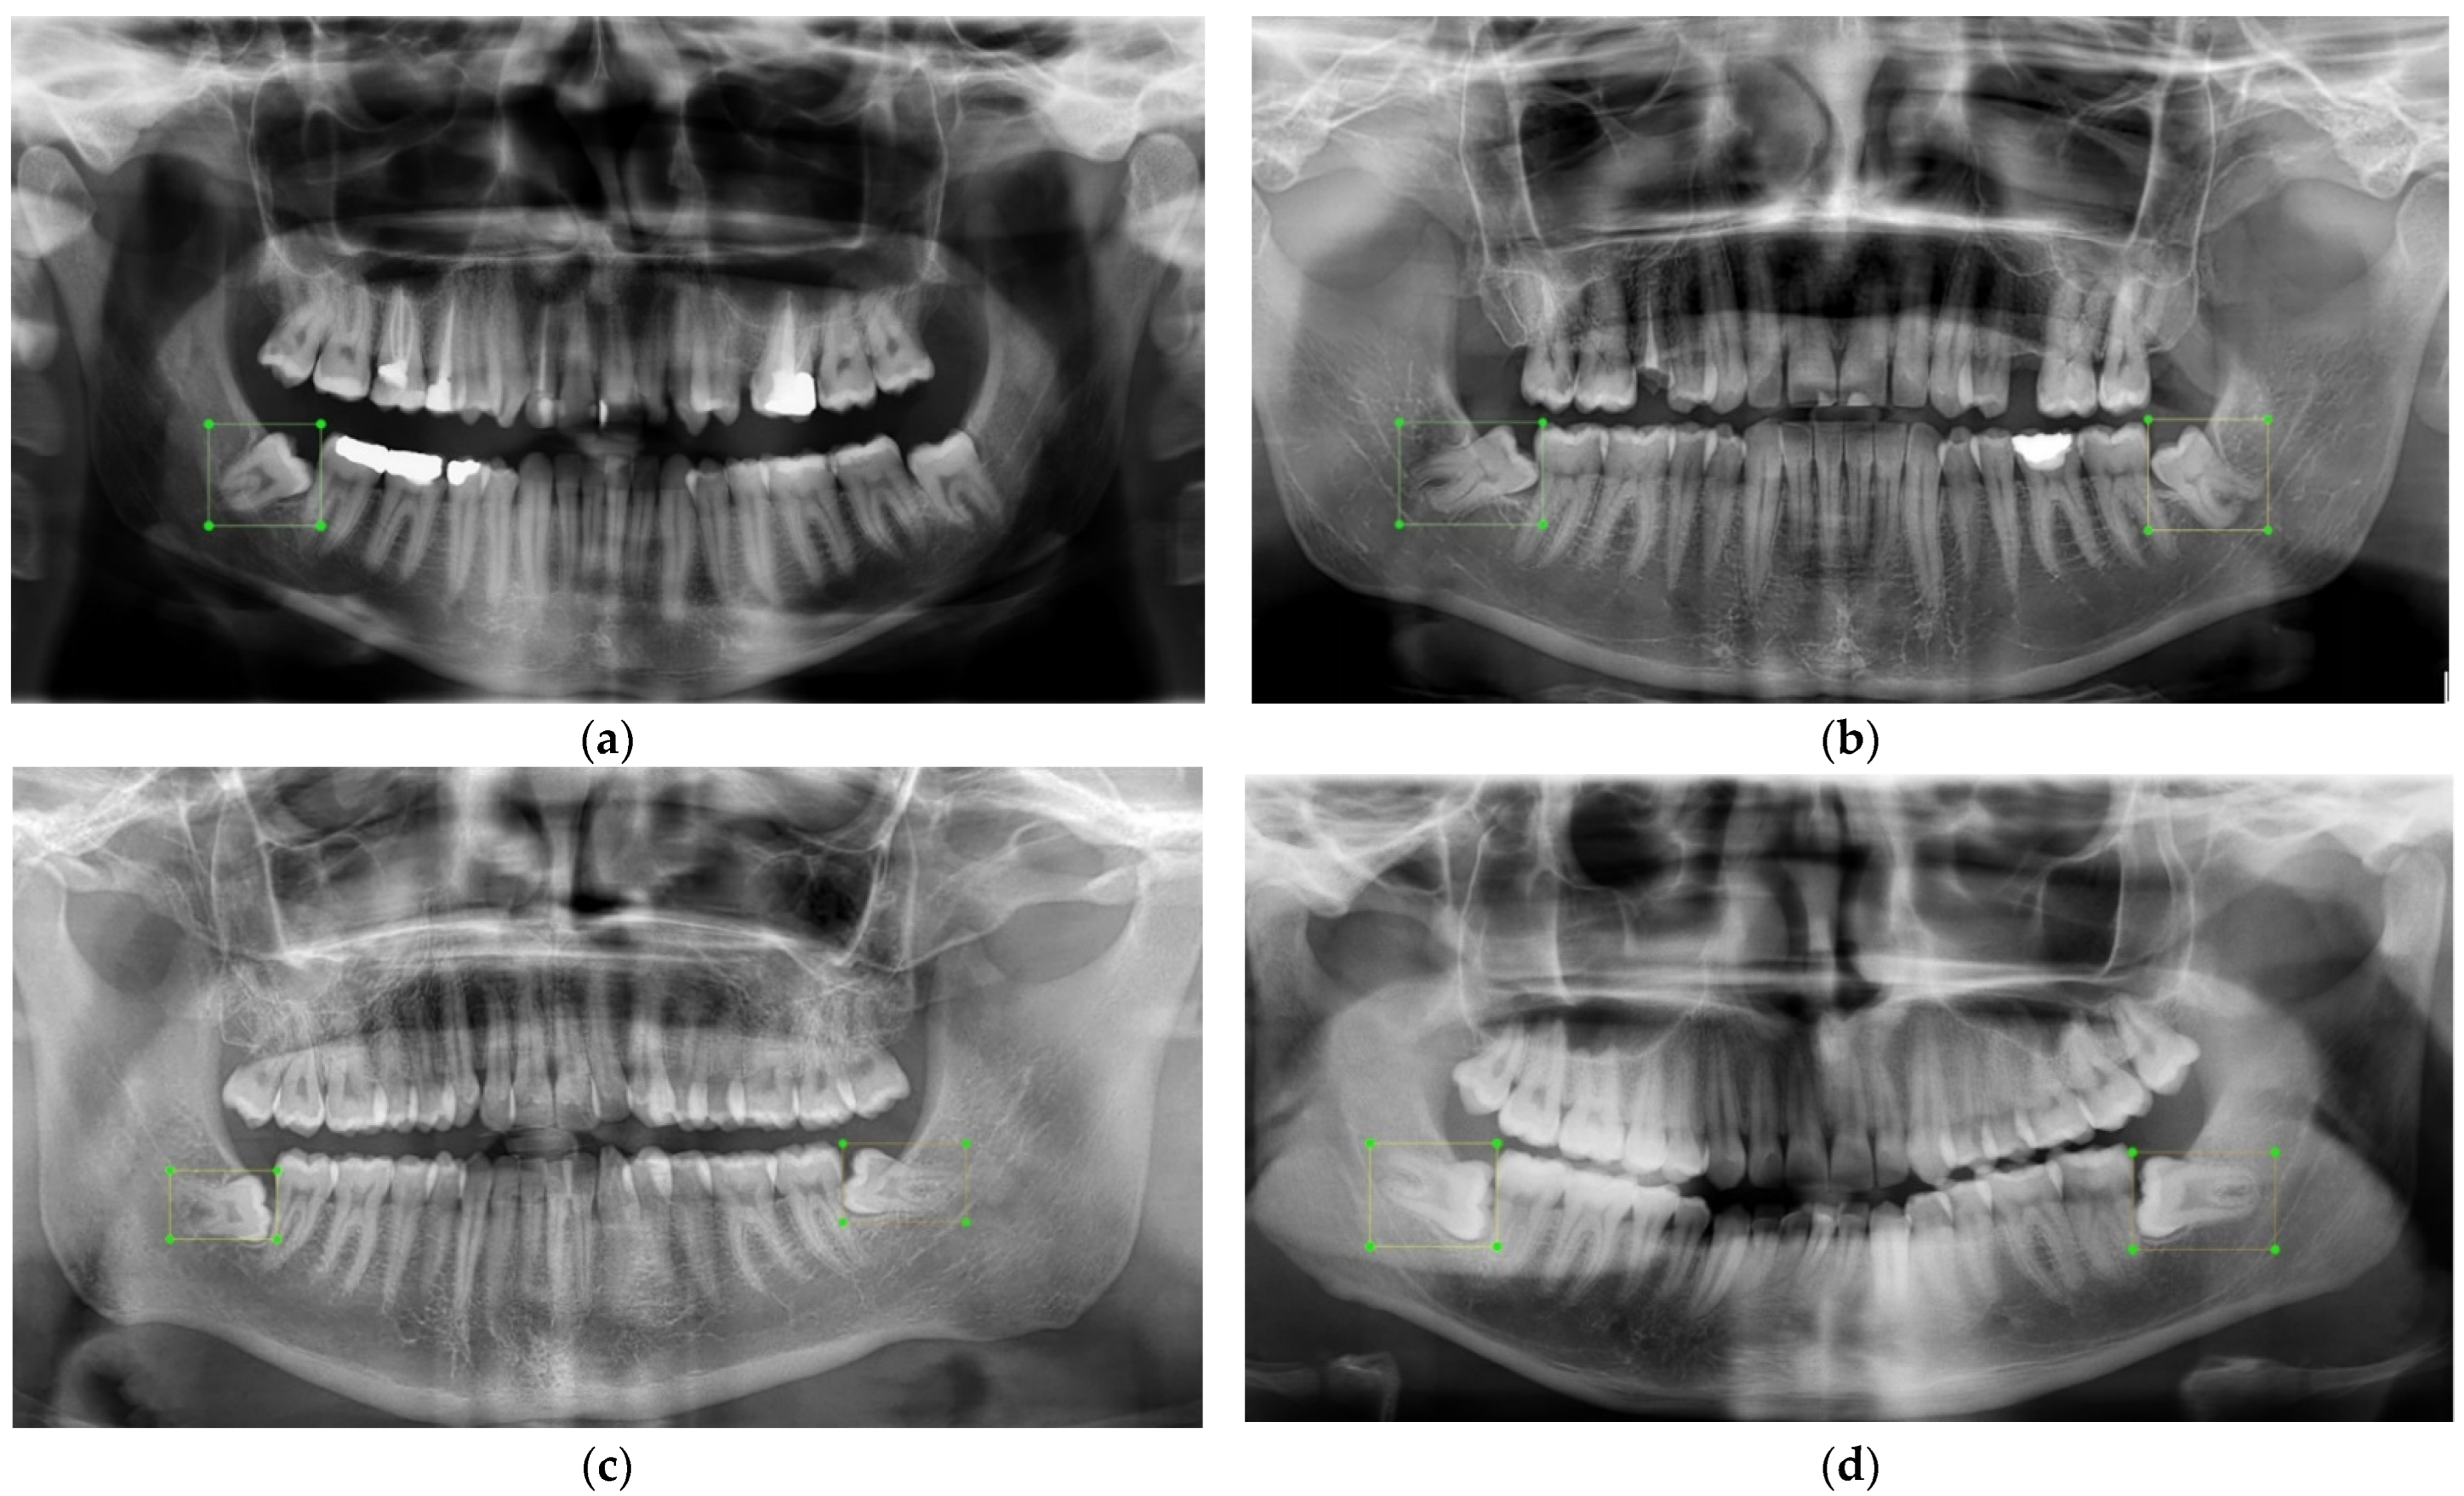

- Tzutalin. LabelImg. Git Code. 2015. Available online: https://github.com/tzutalin/labelImg (accessed on 5 October 2015).